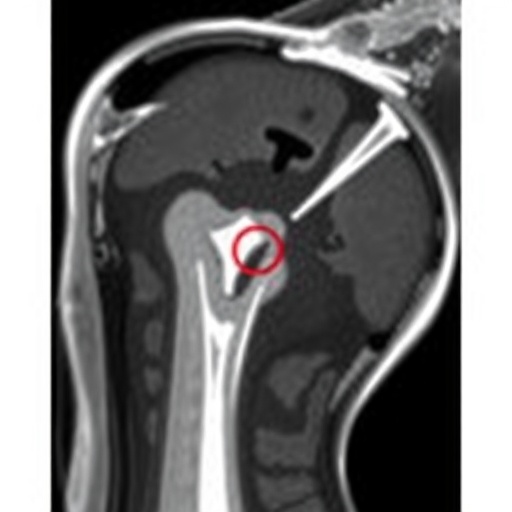

In the realm of pediatric radiology, the challenges posed by diagnosing shoulder conditions in adolescents can often confound even the most experienced clinicians. A recent study highlighted in the journal Pediatr Radiol sheds light on the often ambiguous signals noted in MRIs of the supraspinatus tendon, an integral component in shoulder mechanics and mobility. This analysis by Tung et al. involves a meticulous investigation into the subtleties underlying MRI findings, which can present a diagnostic dilemma for many health professionals in the field.

In this recent study, the authors meticulously explored various aspects of supraspinatus tendon signal alterations. They provide a comprehensive overview of MRI characteristics and their potential implications. The findings indicate a broad spectrum of signal changes that could either reflect normal developmental variations or indicate pathological changes warranting further exploration. Such nuances in MRI interpretations can easily lead to misdiagnosis or unnecessary interventions if not adequately addressed.

Article Title: Supraspinatus tendon signal alterations on adolescent shoulder MRIs: a diagnostic dilemma.